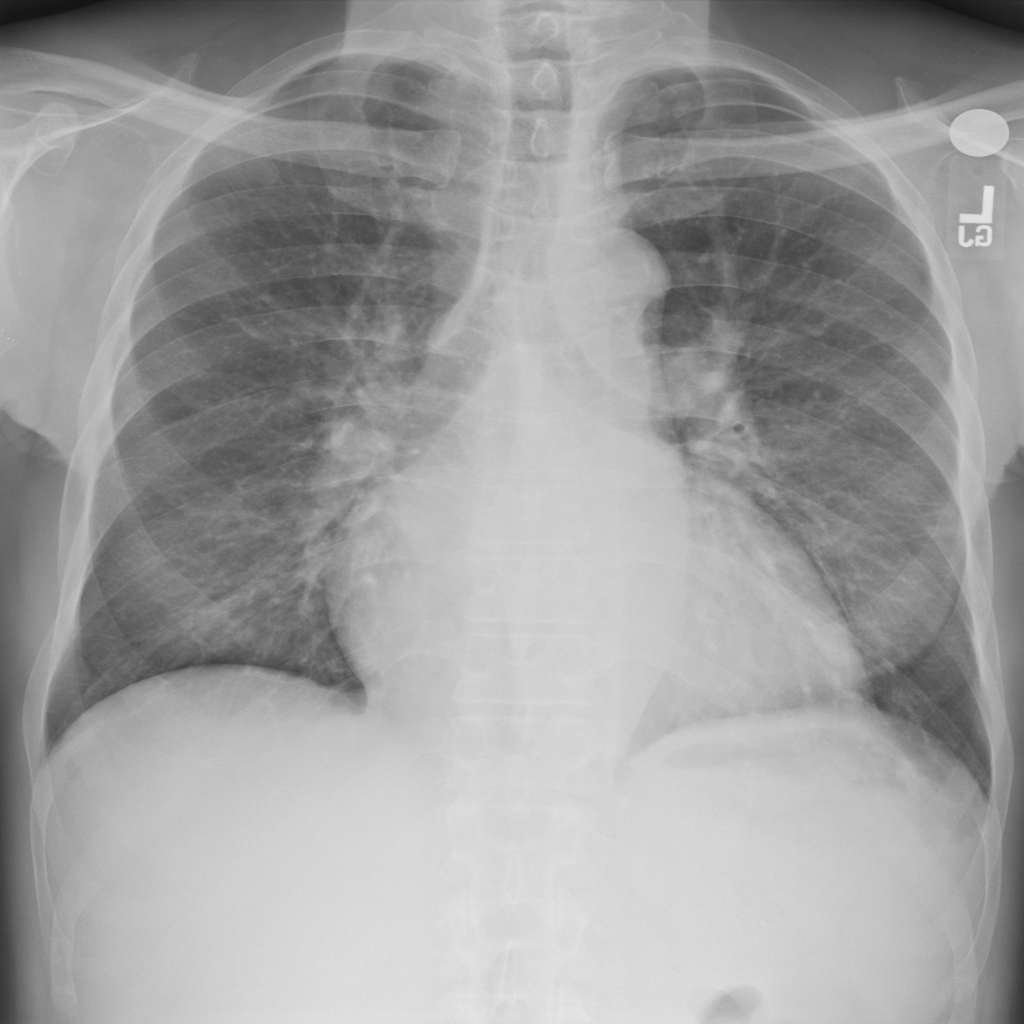

PAT-AE5C · IMG-000Cardiomegaly

PAT-AE5C · IMG-000

PA